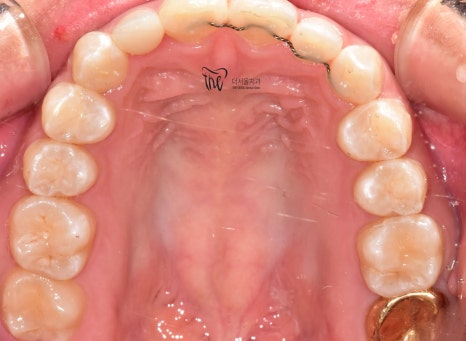

정리해 보면

- 12번 [측절치] = 왜소치

- 앞니 삐뚤거림이 관찰되고 있었으며

이로 인해

- 이 사이 공간이 생길 수 있고

- 앞니 크기 불균형으로 이어질 수 있습니다.

치료 후 모습을 보면

측절치가 서로 대칭인 것을 확인할 수 있으며

앞니가 가지런해 진것을 볼 수 있습니다.